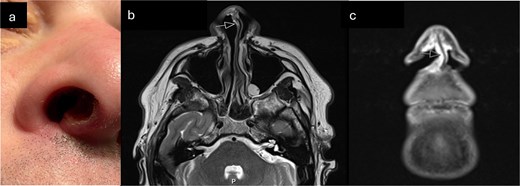

(a) Clinical photograph demonstrating ulcerated lesion of anterior membranous nasal septum (b) T2 axial MRI-arrow indicates soft tissue thickening of columella (c) Coronal STIR MRI sequence—high signal soft tissue thickening extending from columella to right nasal sill (indicated by arrow).

Punch biopsy was obtained under local anaesthetic. Computed tomography was obtained initially, followed by Magnetic Resonance imaging (MRI) (Fig. 1b and c). These demonstrated an abnormally enhancing soft tissue thickening involving the right alar rim, columella, and undersurface of the anterior nasal vestibule. Histological appearances were suggestive of myofibroma but given the clinical and radiological context, differential diagnosis also included low-grade myofibroblastic sarcoma (Figs 2 and 3).